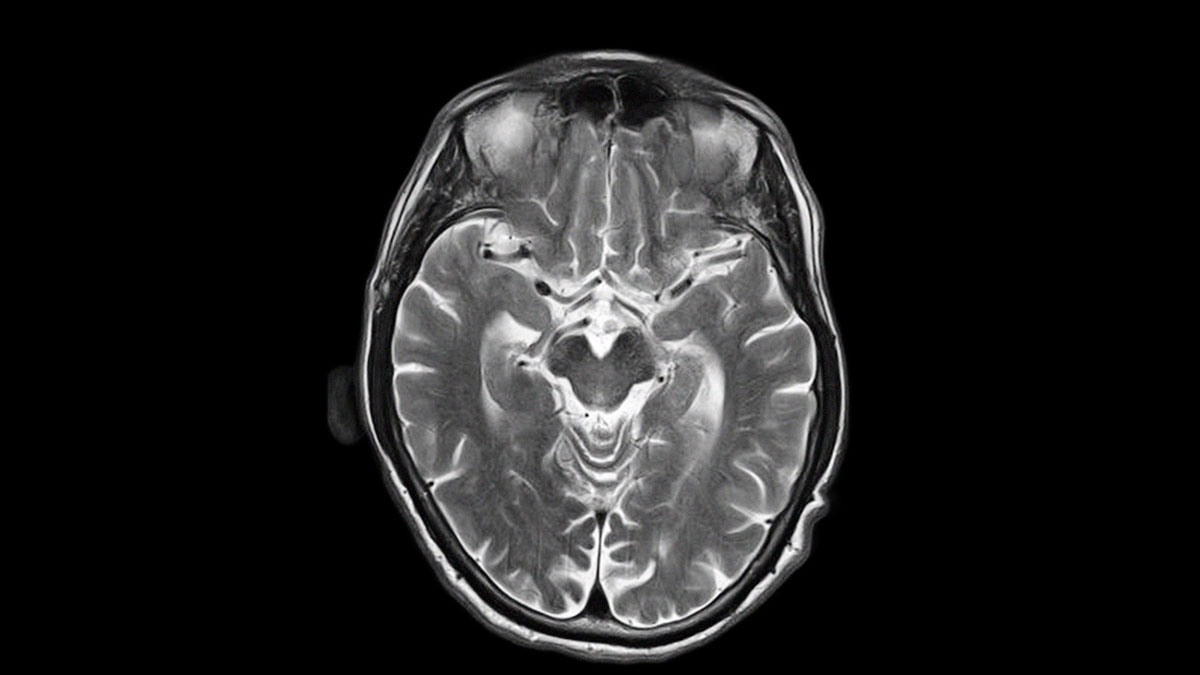

Hace 12 años le diagnosticaron Parkinson a Ricardo, el padre de Natalia; con esa condición se deja de producir Dopamina, neurohormona encargada del movimiento en el cuerpo y la sensación de felicidad. Durante esos años tuvieron una crisis familiar muy fuerte, Natalia les contó también que le gustaban las mujeres. Ella no podía comprender porque a pesar de haber sido militantes de izquierda en su juventud y luchar por la igual y la libertad, no podían aceptar  esa  elección . Hoy una década después, se encuentran a conversar, sobre las ideas de familia, la homosexualidad, las luchas ideológicas y lo que ha significado el avance de la enfermedad de Ricardo.